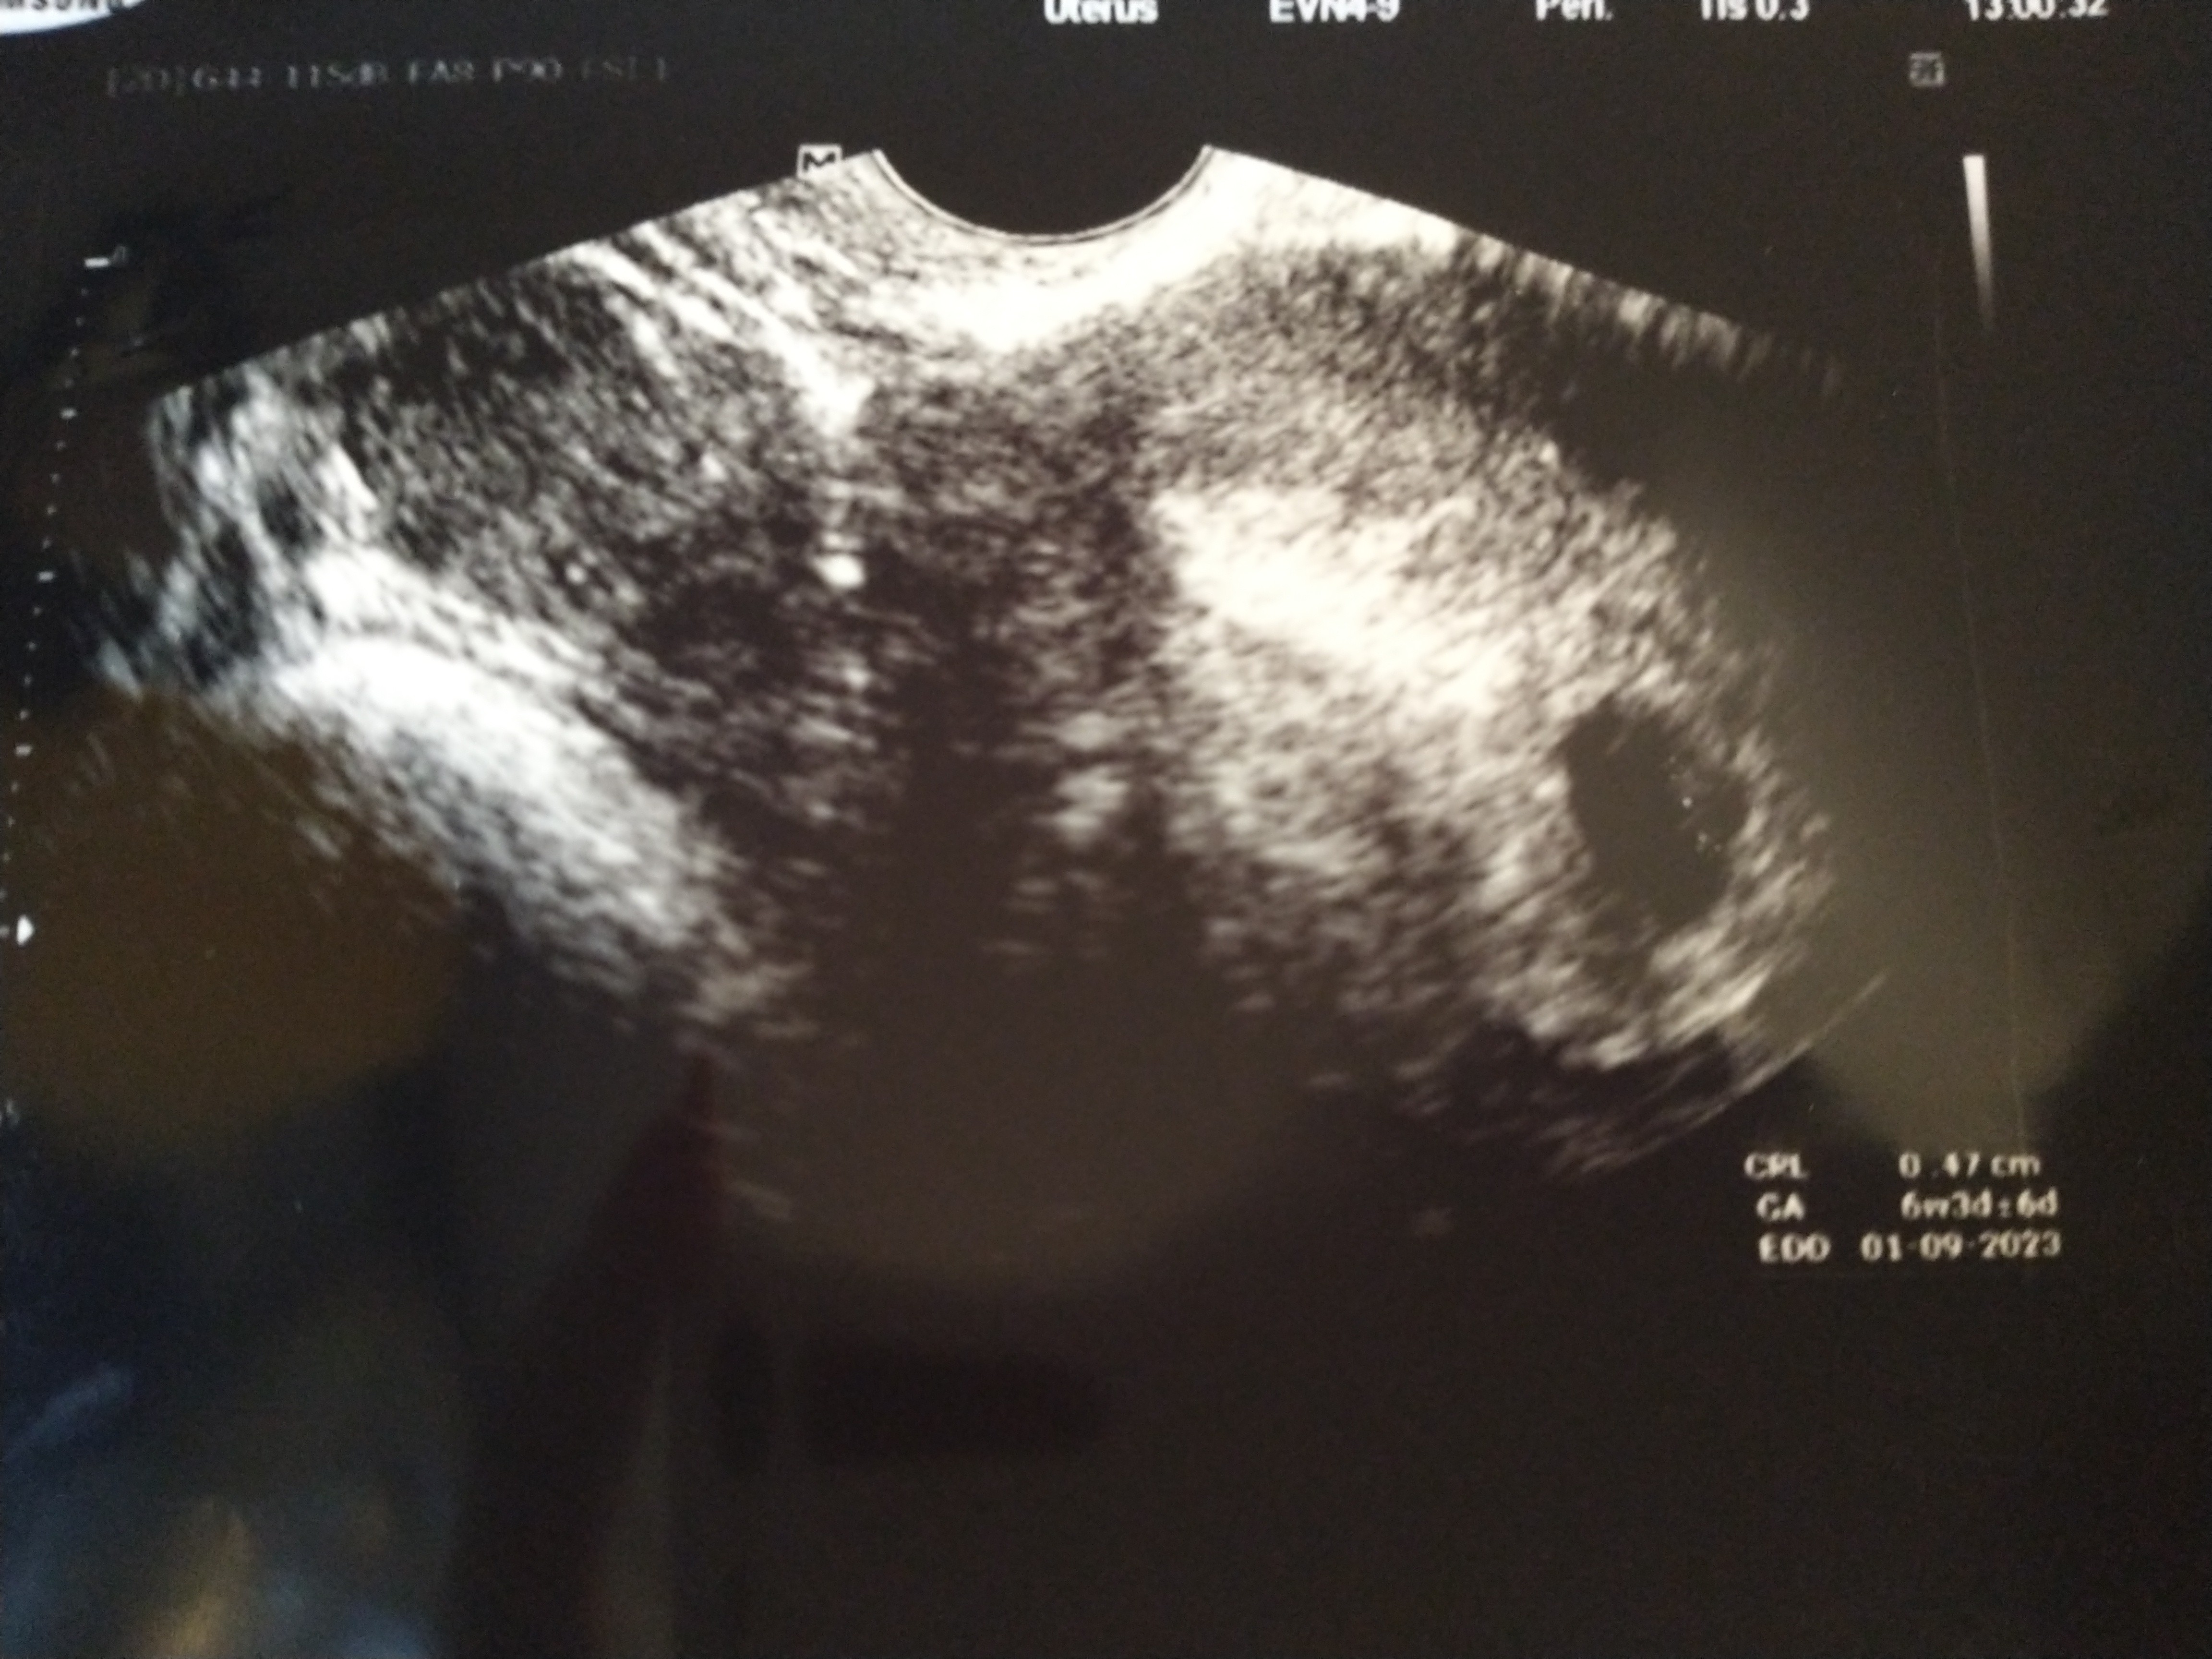

Hejka, jestem dziś po wizycie u ginekologa i USG i okazało, się, że jest maleństwo z bijącym serduszkiem ❤️ lekarz powiedział, żebym sobie głowy HCG nie zawracała i tylko progesteron badała. Wg OM powinien być 8 tydzień a jest 6+2 prawdopodobnie z racji późniejszej owulacji.

Hejka, jestem dziś po wizycie u ginekologa i USG i okazało, się, że jest maleństwo z bijącym serduszkiem ❤️ lekarz powiedział, żebym sobie głowy HCG nie zawracała i tylko progesteron badała. Wg OM powinien być 8 tydzień a jest 6+2 prawdopodobnie z racji późniejszej owulacji. Zobacz załącznik 1482847